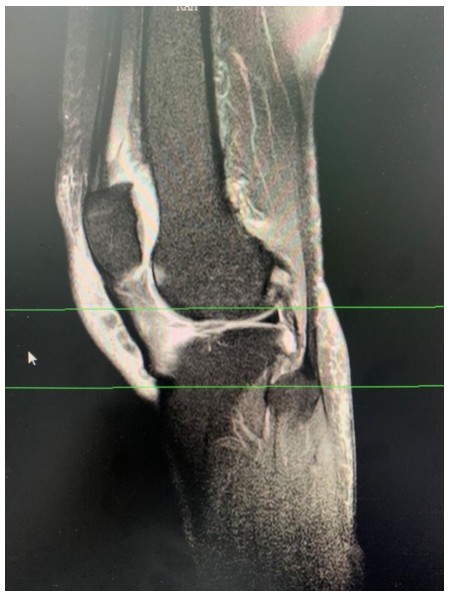

近日,衡陽市中心醫(yī)院華新院區(qū)疼痛門診接診了兩位年齡相仿、癥狀相似的女性患者,兩人都因一側(cè)膝關(guān)節(jié)腫脹、變形,疼痛難忍、下蹲受限、步行困難嚴(yán)重影響生活前來求診。兩位患者分別經(jīng)過張娟、趙夢岑兩位主治醫(yī)生的診治后被診斷為膝關(guān)節(jié)退變,并且發(fā)現(xiàn)患膝側(cè)關(guān)節(jié)內(nèi)存在大量積液。

膝關(guān)節(jié)炎是一種以退行性病理改變?yōu)榛A(chǔ)的疾患,好發(fā)于中老年人群,其癥狀多表現(xiàn)為膝關(guān)節(jié)腫痛、坐起立行時(shí)膝部酸痛不適等,偶有腫脹、彈響、積液等表現(xiàn)。如不及時(shí)治療則會導(dǎo)致關(guān)節(jié)畸形或殘疾。專家提醒,患有膝關(guān)節(jié)炎請及時(shí)到正規(guī)醫(yī)院就醫(yī),切莫因拖延耽誤了治療時(shí)機(jī)。